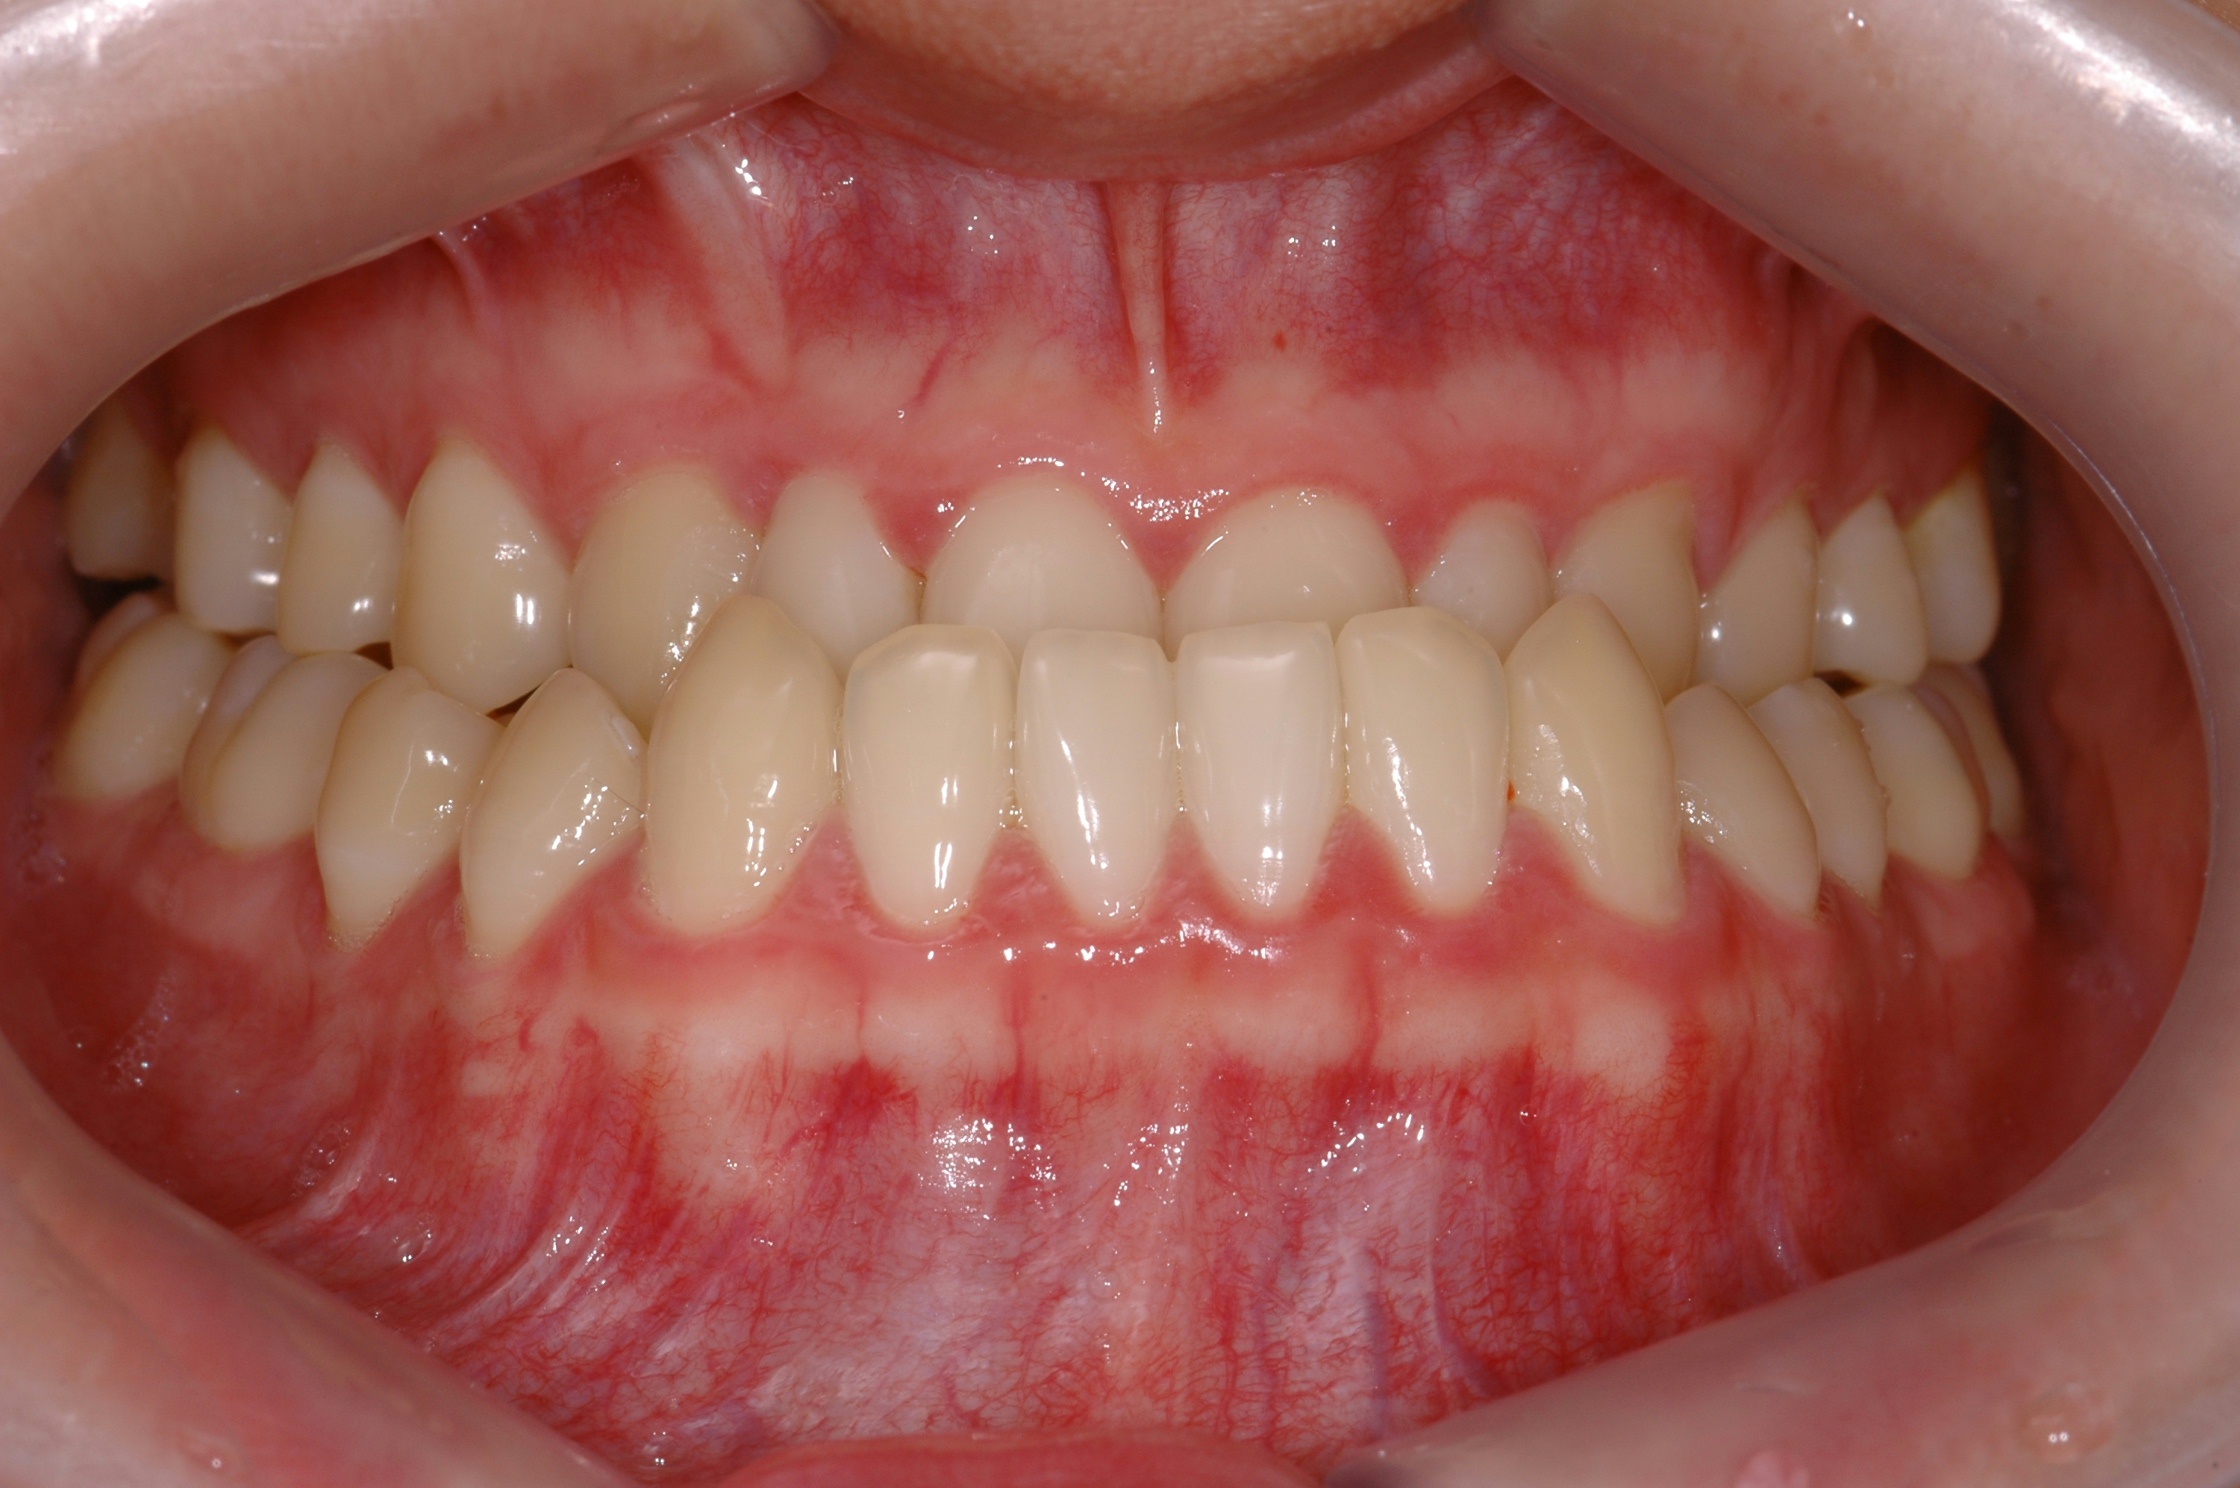

치료 전 사진입니다.